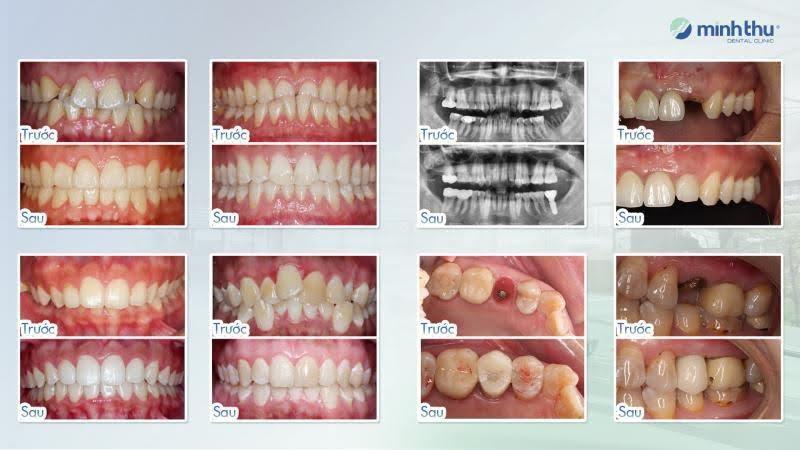

Nha khoa Minh Thu – Hơn 35 năm lời khẳng định bền vững

Gọi điệnThành lập ngày 19/12/1989 bởi Bác sĩ Hà Minh Thu – Nguyên Trưởng khoa Nắn chỉnh răng Viện Răng Hàm Mặt Trung ương, Trưởng bộ môn Nắn chỉnh răng ĐH Răng Hàm Mặt, Nha khoa Minh Thu là một trong những phòng khám nha khoa đầu tiên tại Việt Nam. Từ năm 1994, Minh Thu đã tiên phong thực hiện kỹ thuật nắn chỉnh răng cố định, đồng thời triển khai cấy ghép Implant và dán sứ Veneer sớm nhất tại Việt Nam (từ năm 2005). Đặc biệt, từ năm 2014, Minh Thu trở thành một trong những đối tác đầu tiên của Invisalign tại Việt Nam. Trải qua hơn 35 năm phát triển, nha khoa đã điều trị thành công cho hàng chục nghìn khách hàng, mang lại hàng ngàn nụ cười KHỎE – ĐẸP – BỀN VỮNG.

Lý do nên chọn Nha khoa Minh Thu:

- Bề dày lịch sử và uy tín: Với hơn 35 năm hoạt động, hàng chục nghìn ca niềng răng, implant, và veneer được thực hiện thành công, khẳng định chất lượng điều trị vượt trội.

- Đội ngũ bác sĩ chuyên môn cao: Các bác sĩ đều tốt nghiệp từ các trường đại học danh tiếng, là thành viên các hiệp hội nha khoa hàng đầu như WFO, EAS, AAO, IDC, ITI.

- Cơ sở vật chất hiện đại: Sở hữu 3 cơ sở tại trung tâm Hà Nội (Hai Bà Trưng, Cầu Giấy, Long Biên), được trang bị công nghệ tiên tiến như máy chụp phim 3D sọ mặt, máy quét iTero Lumina (Mỹ), máy Laser nha khoa, máy nhổ răng siêu âm Piezotome, đảm bảo tiêu chuẩn vô trùng tuyệt đối.

- Kế hoạch điều trị tối ưu: Mỗi ca điều trị được lập kế hoạch cẩn trọng, đảm bảo thẩm mỹ – chức năng – độ bền lâu dài, phù hợp từng cá nhân.

- Trải nghiệm cao cấp: Cơ sở Long Biên với diện tích hơn 1200m² được xem là một trong những phòng khám nha khoa đẹp và hiện đại nhất Việt Nam, mang đến cảm giác thư giãn, thoải mái cho khách hàng.

Thành tựu nổi bật của Nha khoa Minh Thu

- Sáu năm liên tiếp đạt danh hiệu Diamond & Black Diamond Invisalign Provider tại Việt Nam.

- Hàng nghìn ca implant phức tạp được thực hiện thành công.

- Bác sĩ Vũ Đức Tùng – Top 80 bác sĩ Invisalign hàng đầu thế giới, diễn giả tại các hội nghị khu vực Đông Nam Á (2020–2023).

- Nhiều ca Invisalign được chọn trưng bày tại Global Invisalign Gallery và các sự kiện quốc tế.

Với uy tín, chuyên môn sâu và cơ sở vật chất hiện đại, Nha khoa Minh Thu xứng đáng là địa chỉ tin cậy hàng đầu cho hành trình kiến tạo nụ cười khỏe đẹp của bạn.